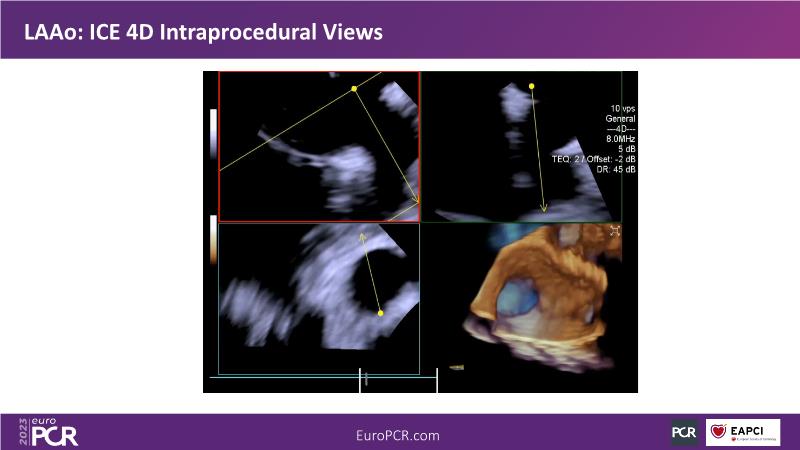

Use of 4D ICE in tricuspid and mitral valve interventions

Watch this session to know the challenges of TV imaging, to get an overview on 4D ICE technology, and to study both a transcatheter tricuspid valve procedure and a transcatheter mitral valve procedure through different case presentations, that will then be discussed.

- To get familiar with the 4D ICE technology and how it can support the imaging and guidance in complex structural heart disease interventions

- To understand the use of 4D ICE and benefits in tricuspid and mitral valve interventions